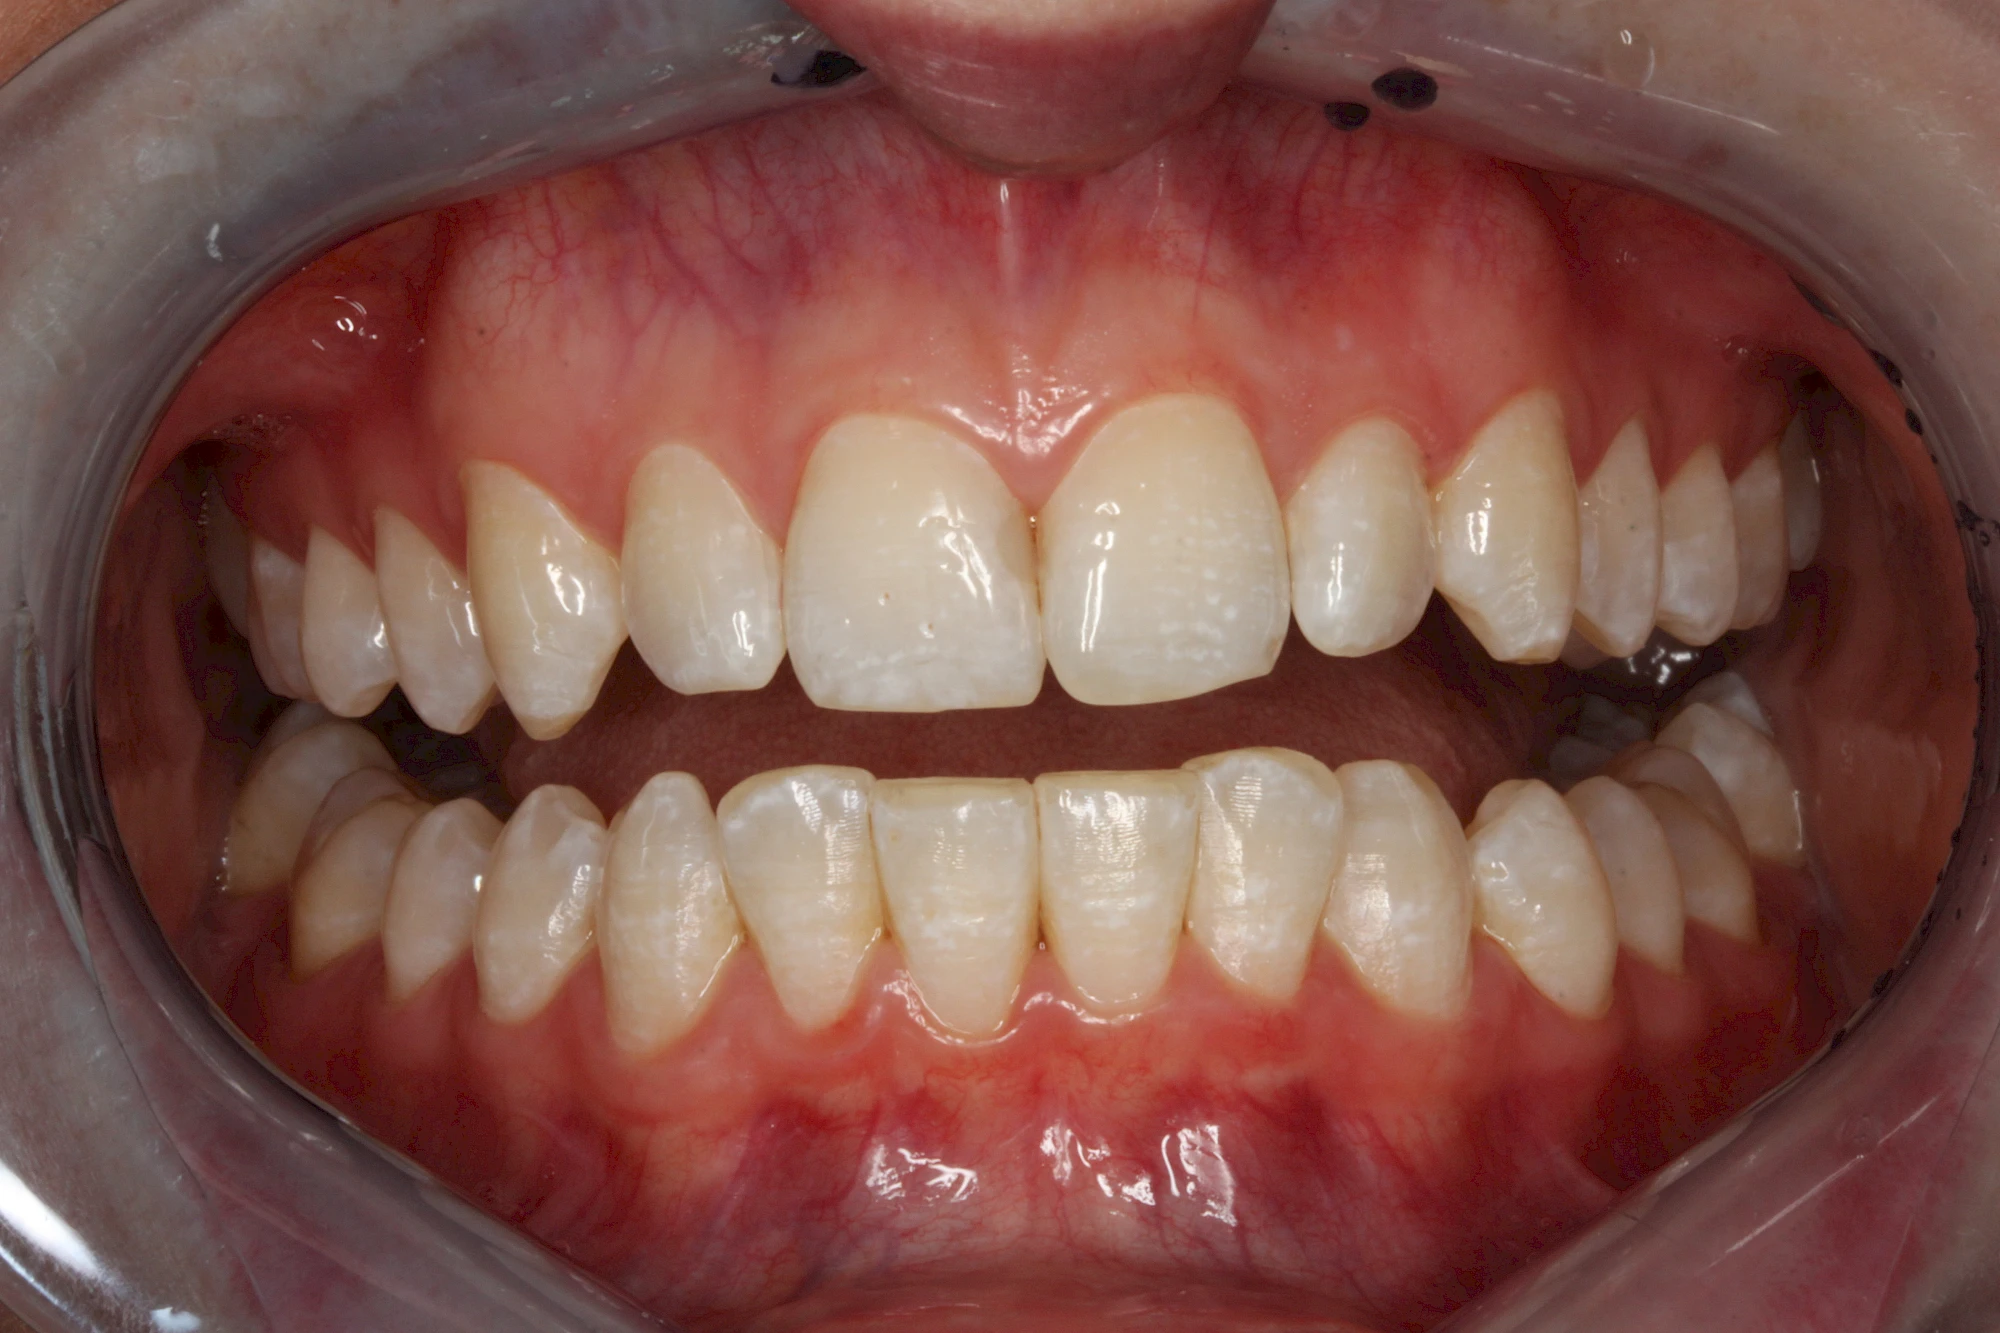

Verfärbungen an Zähnen können außen aufgelagert oder im Zahn eingelagert sein.

Äußere Verfärbungen durch Genußmittel oder Medikamente (Eisen!) lassen sich meist nur durch den Zahnarzt z. B. mit einer professionellen Zahnreinigung entfernen.